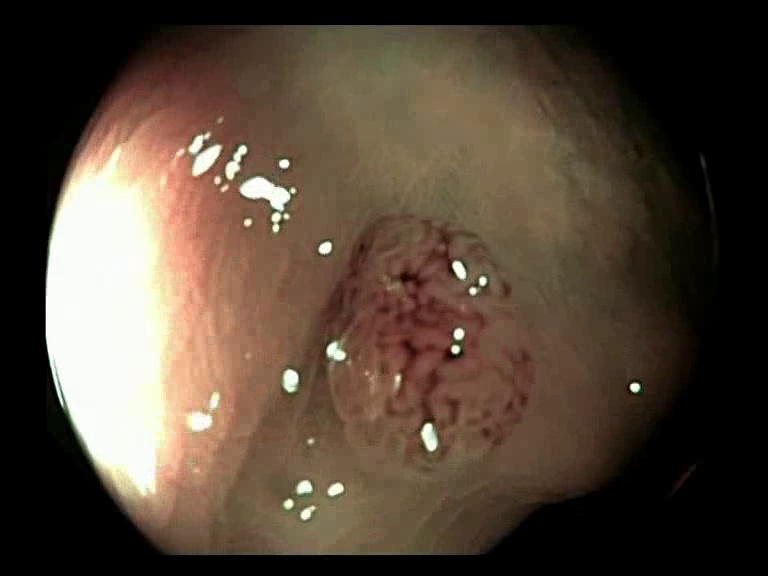

Figure 3: Key-frames obtained by our method and their corresponding depth maps. The polyp is visible from different viewing angles in these selected frames.

The selected key-frames are finally used to reconstruct the 3D surface of the polyp. We have used Facebook’s 3D image GUI to view the reconstructed polyp surface, the link to the video is shown here: https://youtu.be/PJKfk0Mqu2I\href https://youtu.be/PJKfk0Mqu2I. 3D visualization of a polyp helps in surgeries involving the removal of the polyp from its root. This gives better visualization of polyps for diagnosis. Fig. 3 shows some of the results of key-frame extraction and the corresponding depth maps. No publicly available datasets or methods using them that predict depth maps from endoscopic frames exist. Thus, a comparison between different methods for predicting depth from endoscopic images couldn’t be performed.